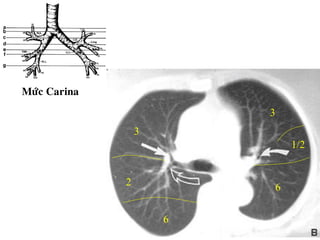

Ngang möùc cung

ñoäng maïch chuû

3

2

1/2

1

6

Möùc Carina

Möùc ñoäng

maïch phoåi (T)

maïch phoåi (P)

• Ngang möùc carina: thaáy ñoäng maïch phoåi (T), thaáy

pheá quaûn (P) chia cho thuøy treân baét ñaàu thaáy

phaân thuøy 6 (P).

• Ngang möùc ñoäng maïch phoåi (P): thaáy pheá quaûn (T)

chiaheát thuøy treân xuaát hieän thuøy giöõa, thuøy

löôõi.

• Ngang möùc nhó (T): pheá quaûn (P) chia thuøy giöõa-

döôùi heát phaân thuøy 6 phaân thuøy 8,9,10.

• Ngang möùc 4 buoàng heát haï phaân thuøy 4 (T).